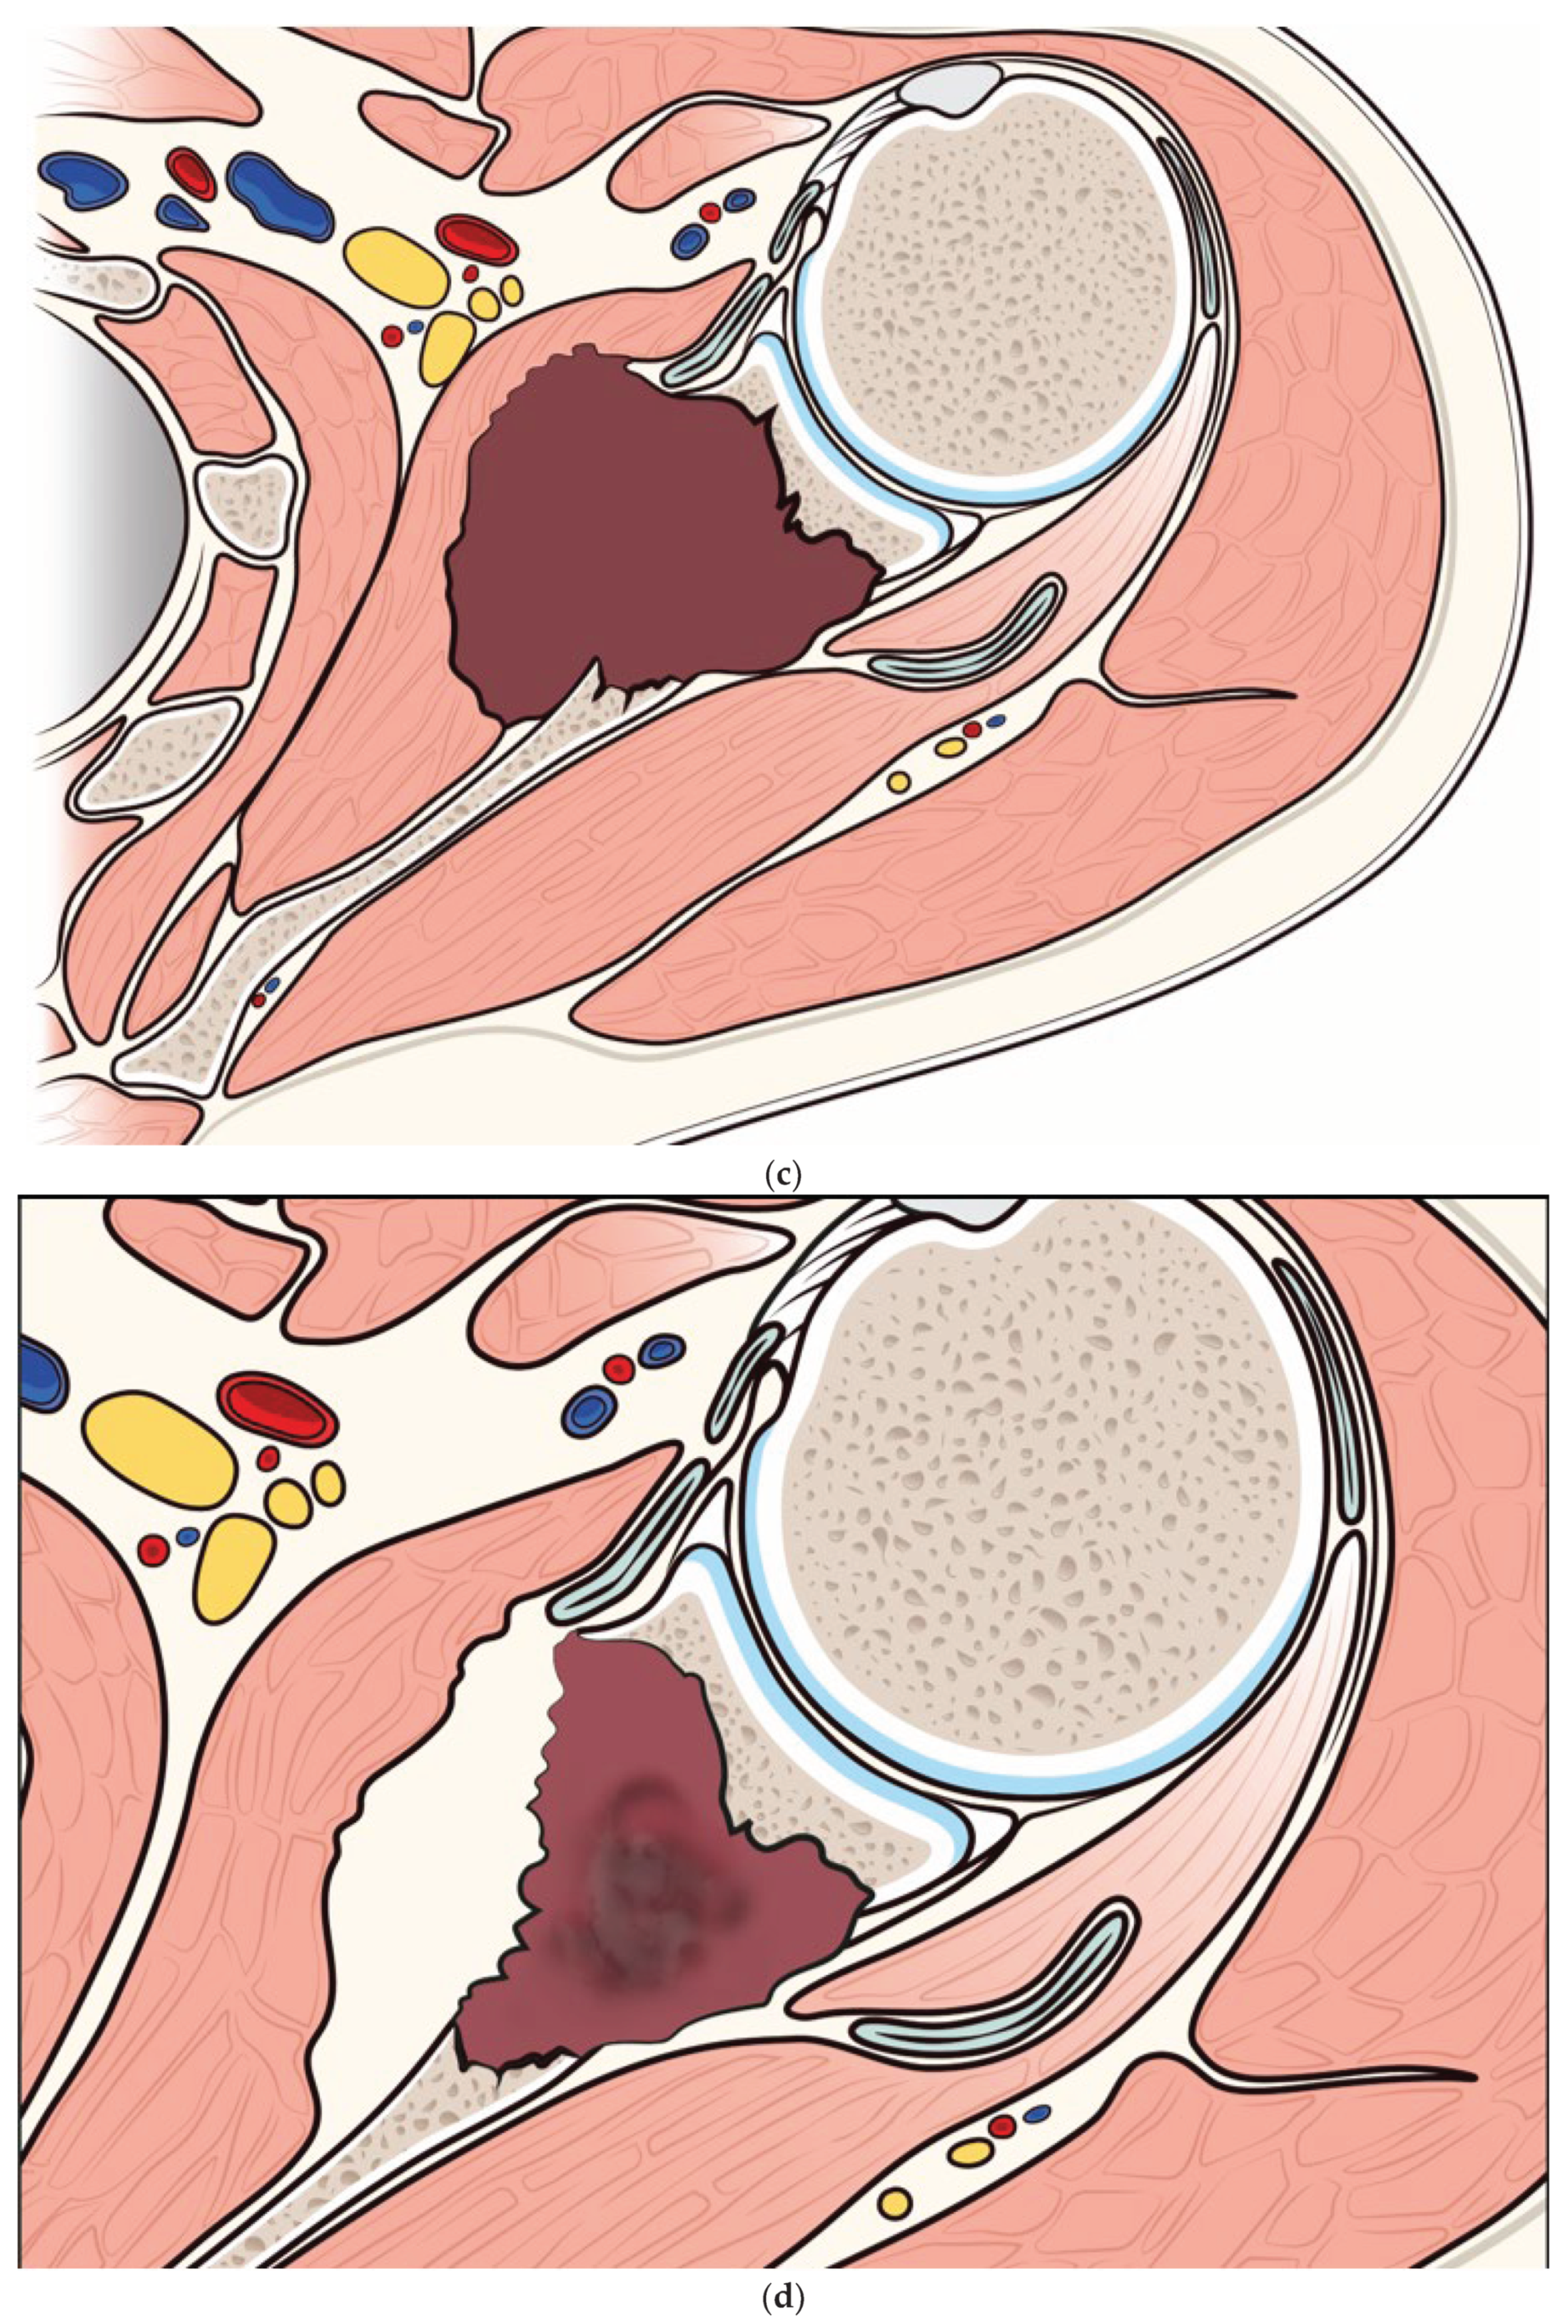

Metastatic tumor size was reduced from a mean of 192.2 cm3 (range 38.7 to 480.1 cm3) pre-embolization to a mean of 177.3 cm3 (range 37.2 to 455.5 cm3) at the 12-month follow-up (p<0.05) (Figure 3). None of the patients experienced embolization-related complications.

Figure 3. a) Pre-embolization CT showing a metastatic lesion from renal cancer in the body of the scapula and b) 12-month post-embolization CT showing increased ossification of the lytic lesion of the scapula, with significant reduction of extraskeletal pathologic tissue. c) and d) illustration of the evolution of a metastatic lesion of the scapula before and after arterial embolization.